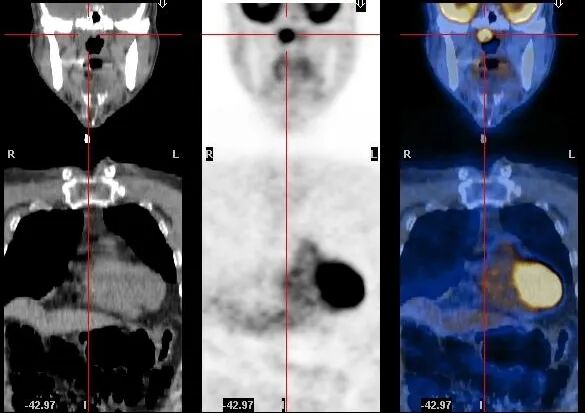

食管癌伴淋巴结、骨、肝脏转移

图片